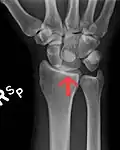

Dislocated lunate -